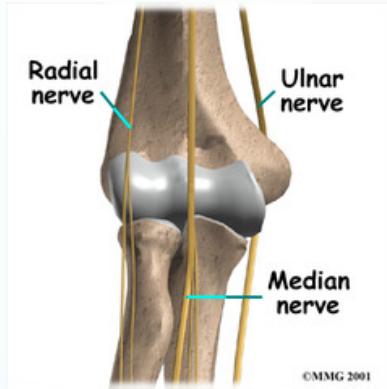

Nerve injury: Median, Radial - Test: Oppose thumb with little finger

- Test: Flex/extend fingers/wrist

Vascular injury: Brachial artery - (tenting, kinking) - only by touching the artery the patient feels spasm in distal part of forearm